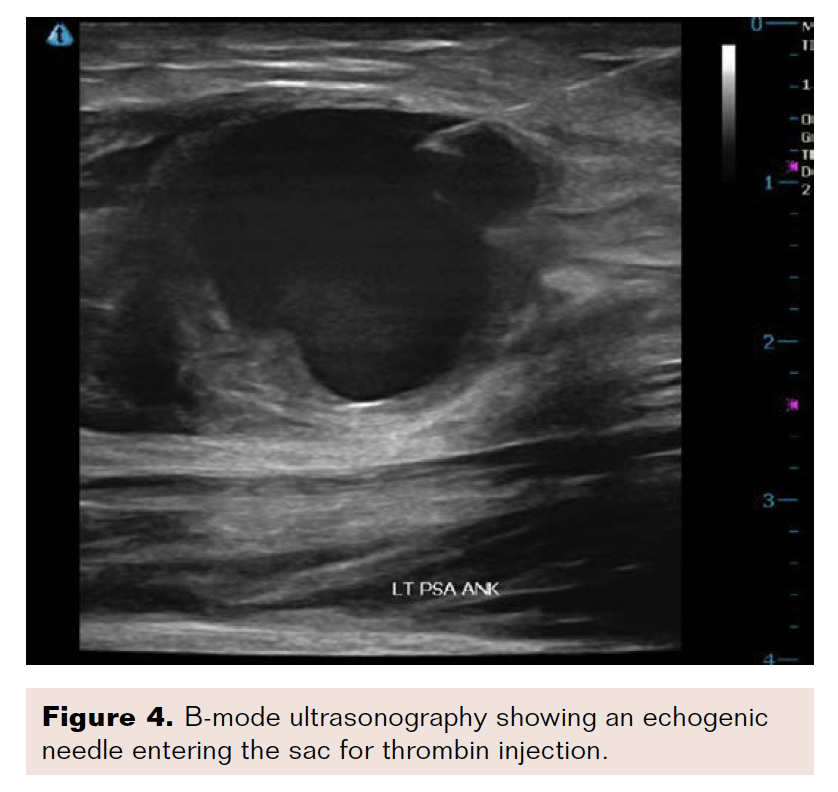

Ultrasound-guided passage of a 25-gauge needle into the superficial portion of the pseudoaneurysm was performed using real-time ultrasonography (Figure 3). A total of 0.4 mL of 1000 units/mL (400 units) of recombinant thrombin was injected with near immediate thrombosis of the dominant sac (Figure 4). A second component of the pseudoaneurysm, located more centrally, was identified near the neck. There was no clear window, except through the dominant sac. Using a longer, 22-gauge needle, access was gained into the more central lesion, and an additional 0.3 mL (300 units) of thrombin was injected, causing thrombosis in the region.